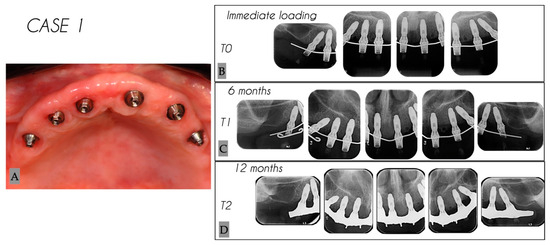

| 1 | Female | 54 | Maxilla | 6 |

| Case No. | Tooth No. | Initial MBL (mm) | MBL 6 Months (mm) | MBL 12 Months (mm) | KM 6 Months (mm) | KM 12 Months (mm) |

|---|---|---|---|---|---|---|

| 1 | 25 | 0.12 | 2.51 | 2.73 | 3 | 3 |

| 1 | 23 | 0 | 1.85 | 2.73 | 4 | 4 |

| 1 | 22 | 0.08 | 0.21 | 0.37 | 3 | 3 |

| 1 | 12 | 0.32 | 0.33 | 0.36 | 3 | 3 |

| 1 | 13 | 0 | 0.37 | 0.53 | 4 | 4 |

| 1 | 15 | 0.12 | 2.09 | 2.34 | 4 | 4 |

| Mean | 0.06 | 1.23 | 1.51 | 3.5 | 3.5 | |